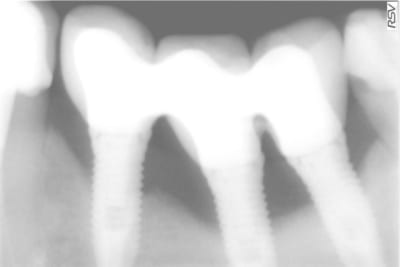

Grossière erreur lors des sutures et exposition de l'os et des implants, malgré tout on continue car belle gencive kératinisée après cicatrisation de ce bordel et résultat au bout de 2 ans ... (entre temps 38 a été virée)

7 oclvjx - Eugenol

9 yufmyr - Eugenol

8 khsxiq - Eugenol

10 hr0uw4 - Eugenol